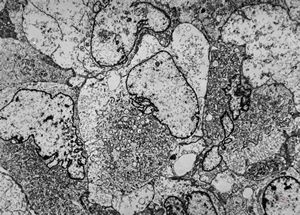

M,40y. | granular cell tumor

F,30y. | granular cell tumor